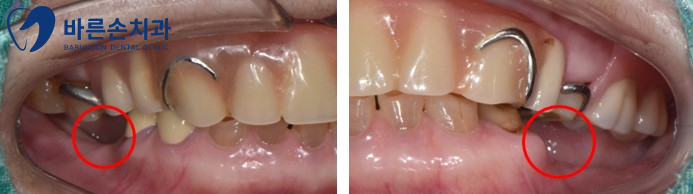

Before 25.03.26

치아가 전반적으로 마모된 모습입니다.

이갈이나 이를 악무는 습관이 있는 분들에게 흔히 나타나는 증상입니다.

증상이 계속되면

교합 이상과 치아 파절이 일어날 수 있습니다.

After 25.07.09

신곡동치과 치료 전, 후 사진을 비교해 보면

치아 길이가 회복되어 진 것이 보입니다.